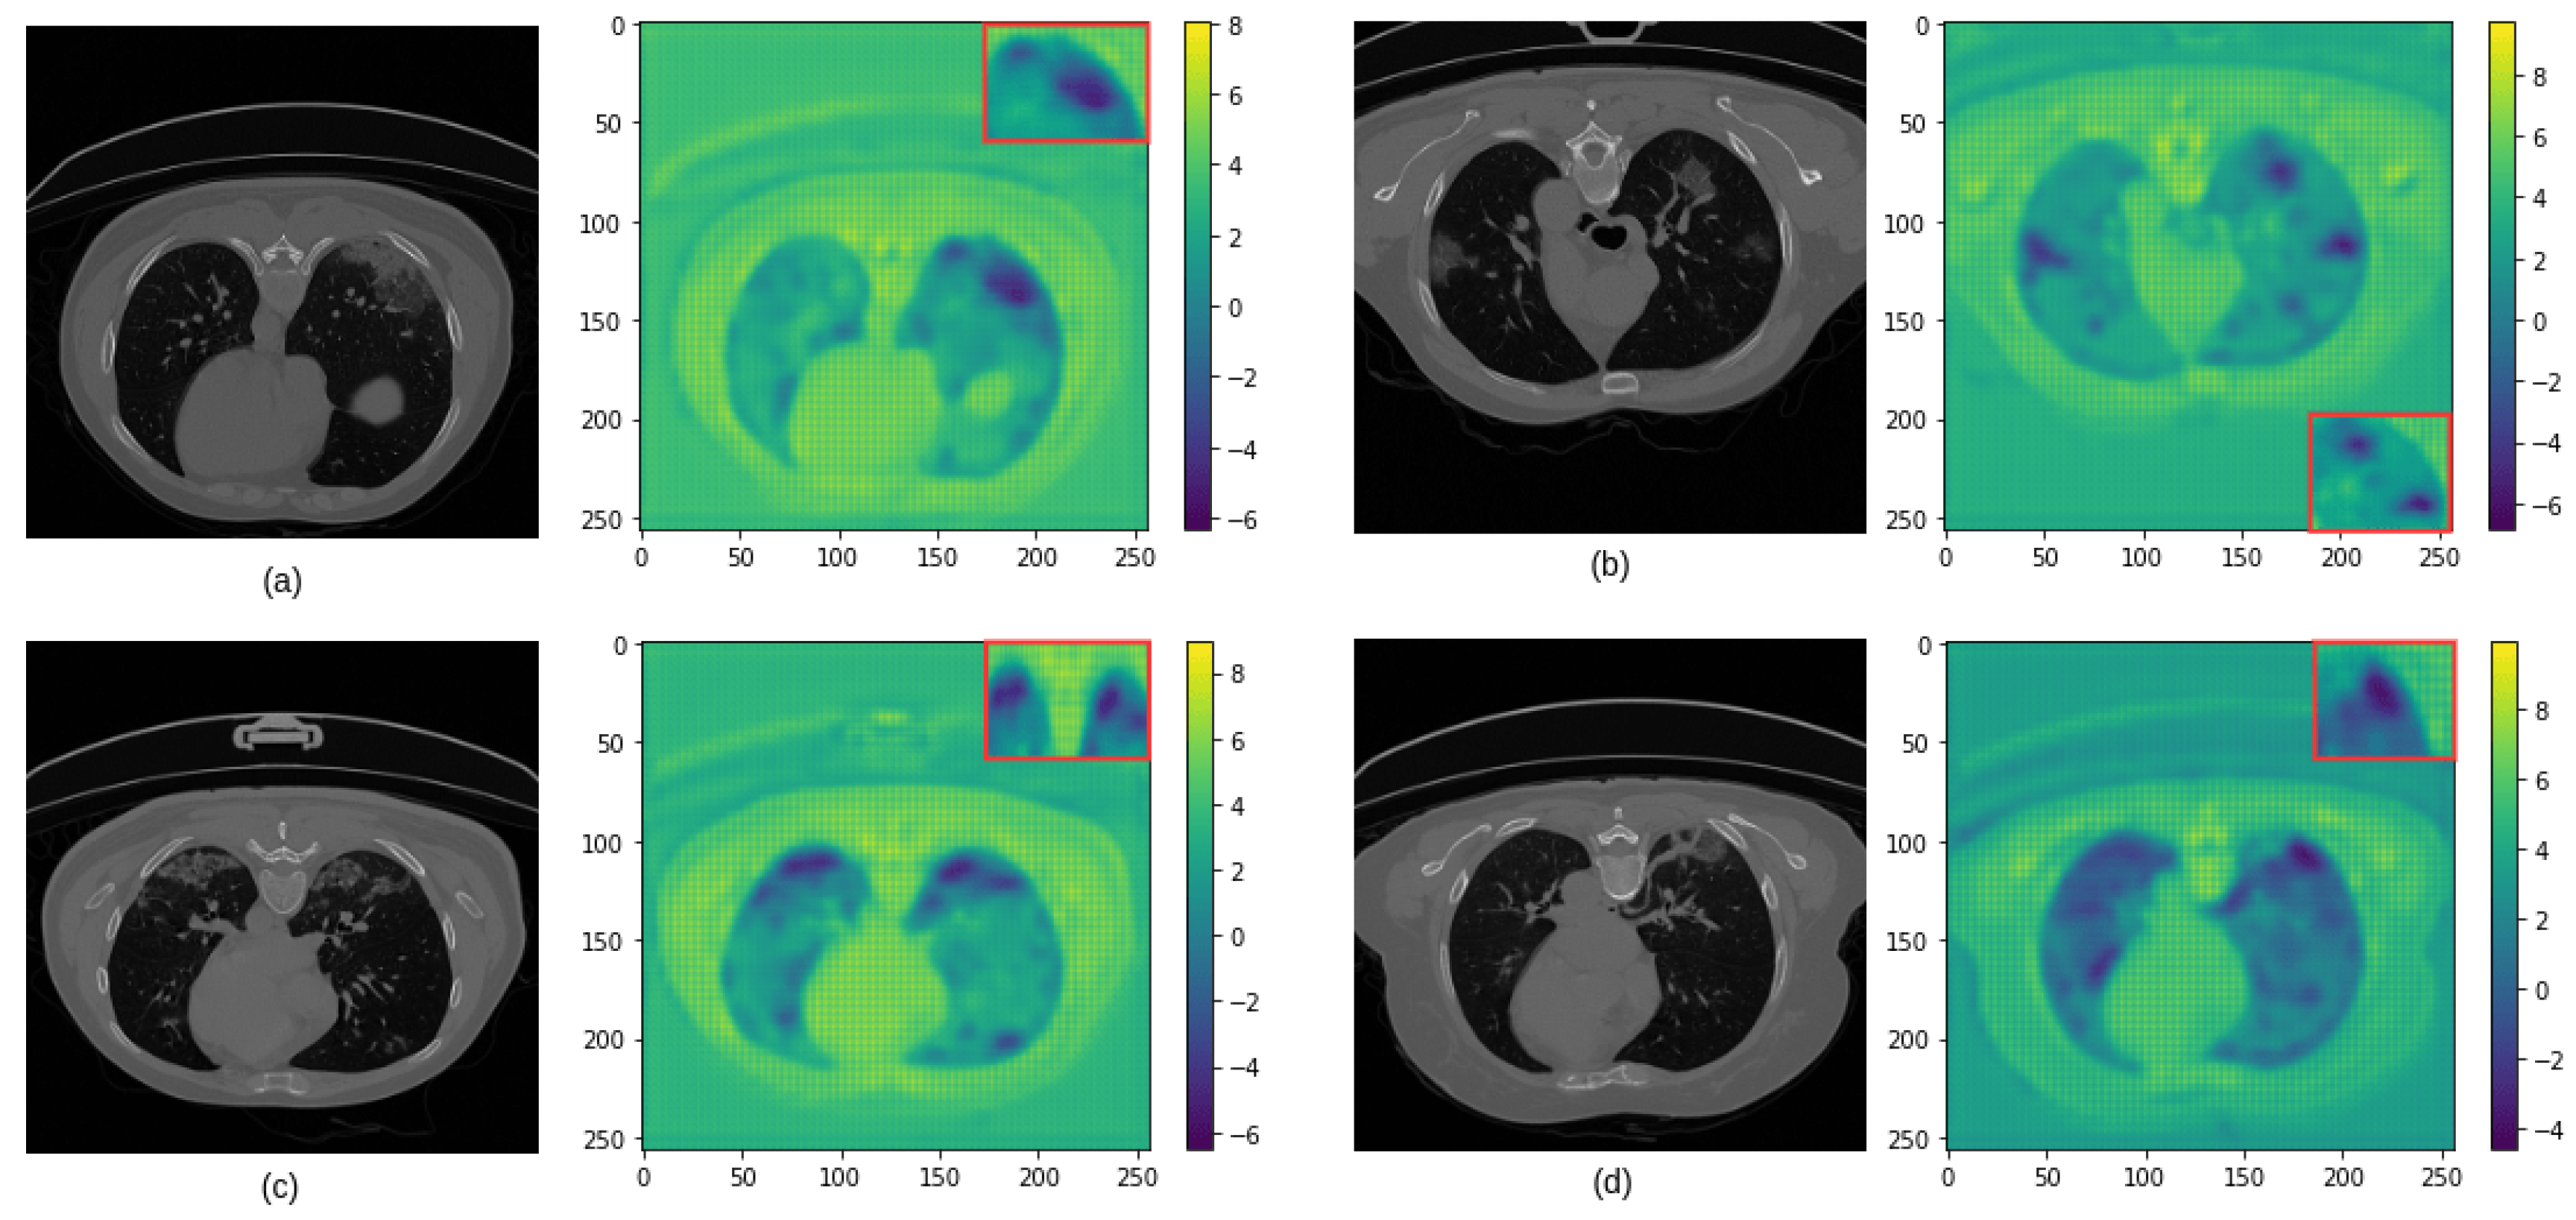

2.1.1. Increasing the Receptive Fields Using Discrete Wavelet Transform (DWT)

3.3. Analysis of the Performance of the Proposed Model